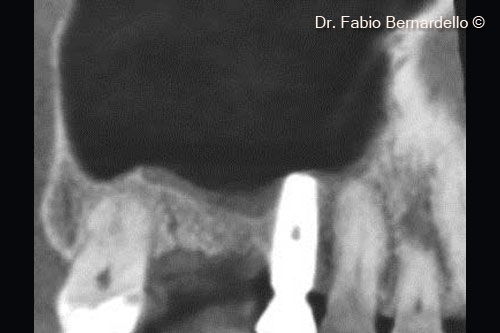

Hình ảnh toàn cảnh xoang hàm trên (Panorex) tại thời điểm ban đầu T0. Gel 40 nâng màng xoang ở vị trí cấy ghép mới và cả phía trên đỉnh của implant cũ ở vị trí số 16

Hình ảnh CBCT mặt cắt ngang tại thời điểm ban đầu (T0). Gel 40 nâng màng xoang tại vị trí cấy ghép mới và cả phía trên đỉnh của implant cũ ở vị trí số 16